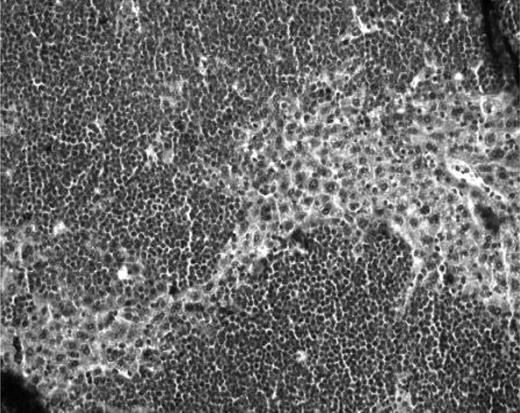

A piece of fresh ovarian tissue was fixed in 4% formaldehyde, embedded in paraffin, and serially sectioned (5-μm-thick sections) at the time of cryopreservation. Every third slide was stained with hematoxylin and eosin (Merck) for histologic evaluation to detect the presence of malignant cells and follicle density.

For each patient, ovarian cortical strips (4 × 1 × 1 mm) were sent for histologic analysis at the time of ovarian tissue cryopreservation. The samples were evaluated by 2 experienced pathologists. By light microscopy, no malignant cells were found in the ovarian tissue of any patients (CML or ALL). Moreover, ovarian follicles were present in all the samples.

Macroscopic and histologic analysis of ovarian fragments recovered from the mice after 6 months' grafting. (A) Macroscopic view of normal frozen-thawed ovarian grafts. (B) Macroscopic view of an enlarged ovarian graft. Note the stitches at both ends. (C) Histologic aspect of a normal ovarian-xenografted fragment. Five ovarian follicles can be recognized in a cellular stroma surrounded by a fibrotic area. Original magnification ×100. (D) Human ovarian graft from a patient with ALL with massive cellular invasion. Note the 6-0 Prolene stitch in the graft (arrow). Original magnification ×50. (E) Human follicle encircled by a large number of lymphocytes. Normal ovarian stroma is no longer present. Original magnification ×100. (F) Massive lymphocytic invasion of the ovarian graft. The histologic abnormalities observed in these lymphocytes were identified as malignant in nature and attributed to leukemic invasion. Original magnification ×200.

In mice grafted with ovarian tissue from CML patients, serial sections of grafts did not show the presence of malignant cells, and human ovarian xenografts had a normal histologic appearance (Figure 2C).

For grafts issuing from ALL patients, 5 of 12 showed obvious invasion by lymphoblasts. Histology confirmed disease in 4 mice presenting with macroscopic signs of malignancy, plus case 18, which exhibited leukemic invasion at microscopic analysis (Figure 2D-F). Figure 2E shows one of these 5 xenografts (case 8), with massive proliferation of malignant lymphocytes, in the middle of which a secondary-stage follicle is clearly visible.